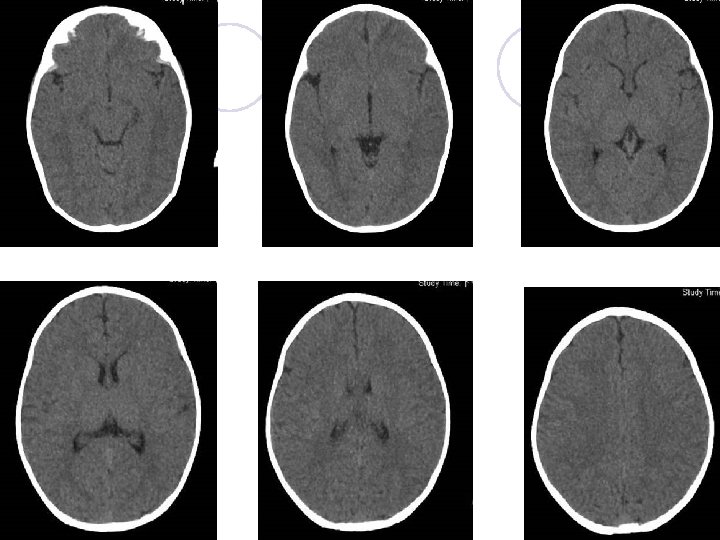

Brain CT